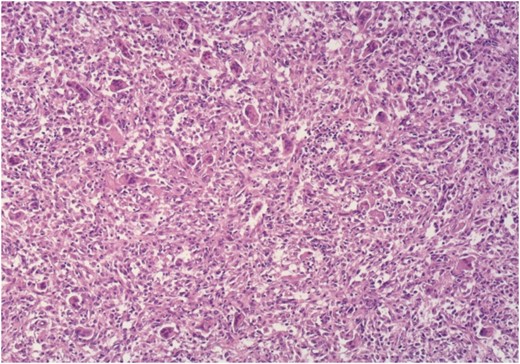

Histology confirmed a recurrence of GCT, composed of numerous multi-nucleated giant cells in-between round to oval mononuclear cells with identical nuclear morphology, with focal collagen deposition, as well as wide areas of recent and older hemorrhage (Fig. 4).